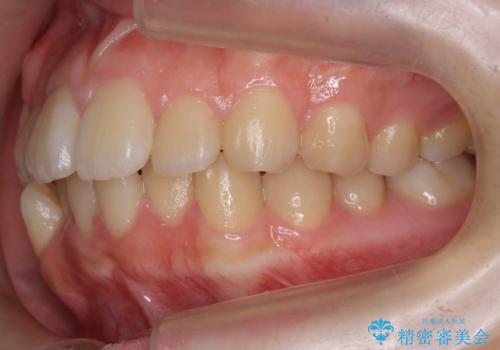

- 歯のがたつきを主訴に来院。

左右とも奥歯のがたつきがあり、左奥はすれ違っていました。

また、右奥は反対咬合になっていました。

インビザライン治療は主に奥歯のかみ合わせが大きな問題がない場合は特に問題なく終了しますが、今回のケースのように奥歯のかみ合わせが悪い場合、しっかり治らないことがあります。

患者様が気づかない範囲で妥協して終わるということをせず、しっかり奥歯に部分矯正を用いて大きな問題を解決してからインビザライン治療に入りました。